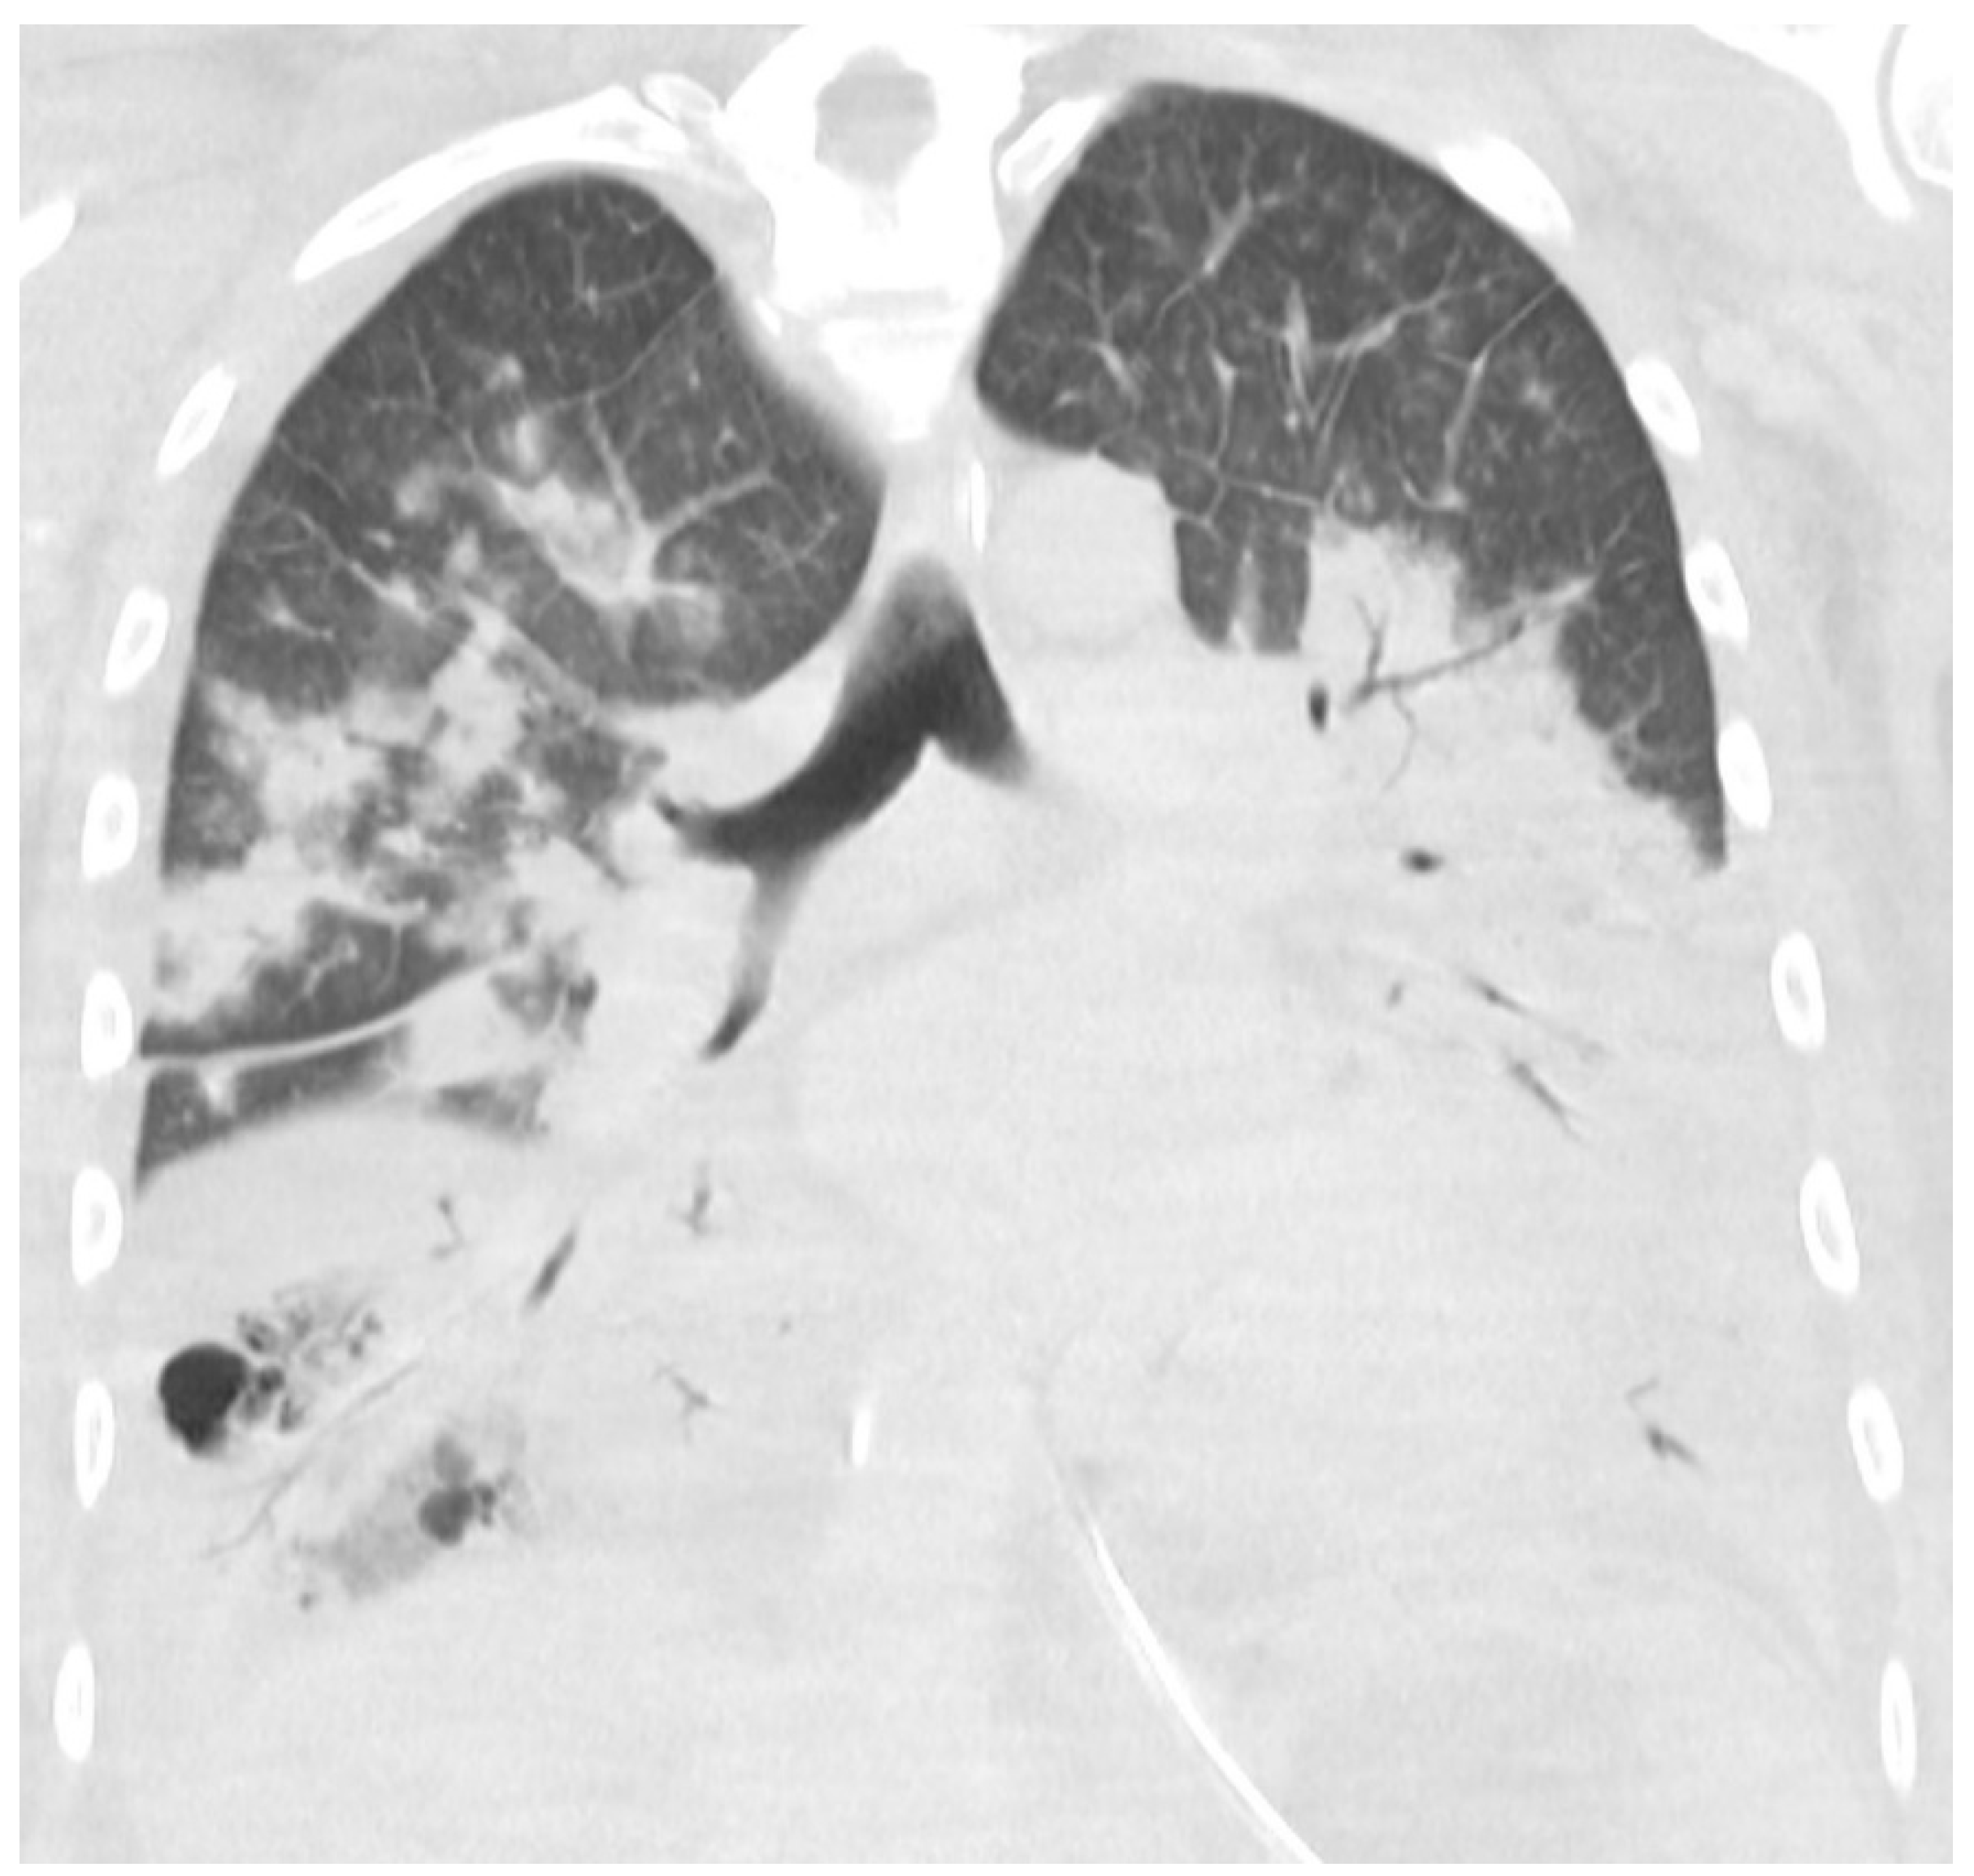

The general practitioner in the Faroe Islands sent him to the radiology department as an out-patient to get a CXR. During the visit to the radiology department, he began to feel lightheaded and nearly fainted. The staff sent him to the emergency department (ED). In the ED, he mentioned that he had felt dyspnoeic and had had productive coughing for 2 days, but that he was feeling better, and the dizziness probably was linked to lack of sleep and exhaustion from the long journey from Colombia to the Faroe Islands. A physical examination revealed a body temperature of 38.9 °C, blood pressure of 134/84 mm Hg, heart rate of 67 beats/min, and oxygen saturation of 98%. The CXR was normal (Figure 1a), and his blood tests showed hemoglobin levels of 7.7 mmol/L, leukocyte levels of 5 × 109/L, and CRP levels of 11 mg/L (Table 1). The patient was a non-smoker and had no history of excessive alcohol consumption. He lived with his wife and children and was a marathon runner in his spare time. The patient was discharged from the ED and advised to contact a doctor if the symptoms worsened or did not get better within a couple of days.

An arterial blood gas test showed a normal pH of 7.40, PaCO2 level of 5.0 kPa, decreased PaO2 level of 9.5 kPa, and elevated lactate level of 3.0 mmol/L. Blood tests showed a hemoglobin level of 8.7 mmol/l, leucocytes level of 1.1 × 109/L, thrombocyte level of 113 × 109/L, creatinine level of 160 µmol/L, and CRP level of 370 mg/L (Table 1). The CXR now showed diffuse bilateral consolidation (Figure 1b). The diagnoses up front were severe community-acquired pneumonia (CAP), septic shock, and ARDS. Disseminated intravascular coagulation (DIC) in progress was first suspected with the symptom of bloody diarrhea in mind, but the blood test results did not suggest severe DIC. The patient was transferred directly to the ICU to get intubated and receive fluid resuscitation, inotrope support, and antibiotic therapy (Table 2).

Figure 1. (a,b) The rapid onset of the severe disease is illustrated here. (a) shows a normal CXR from day 1, 2 days prior to admission. (b) shows a CXR with diffuse consolidation on the day of admission (day 3).